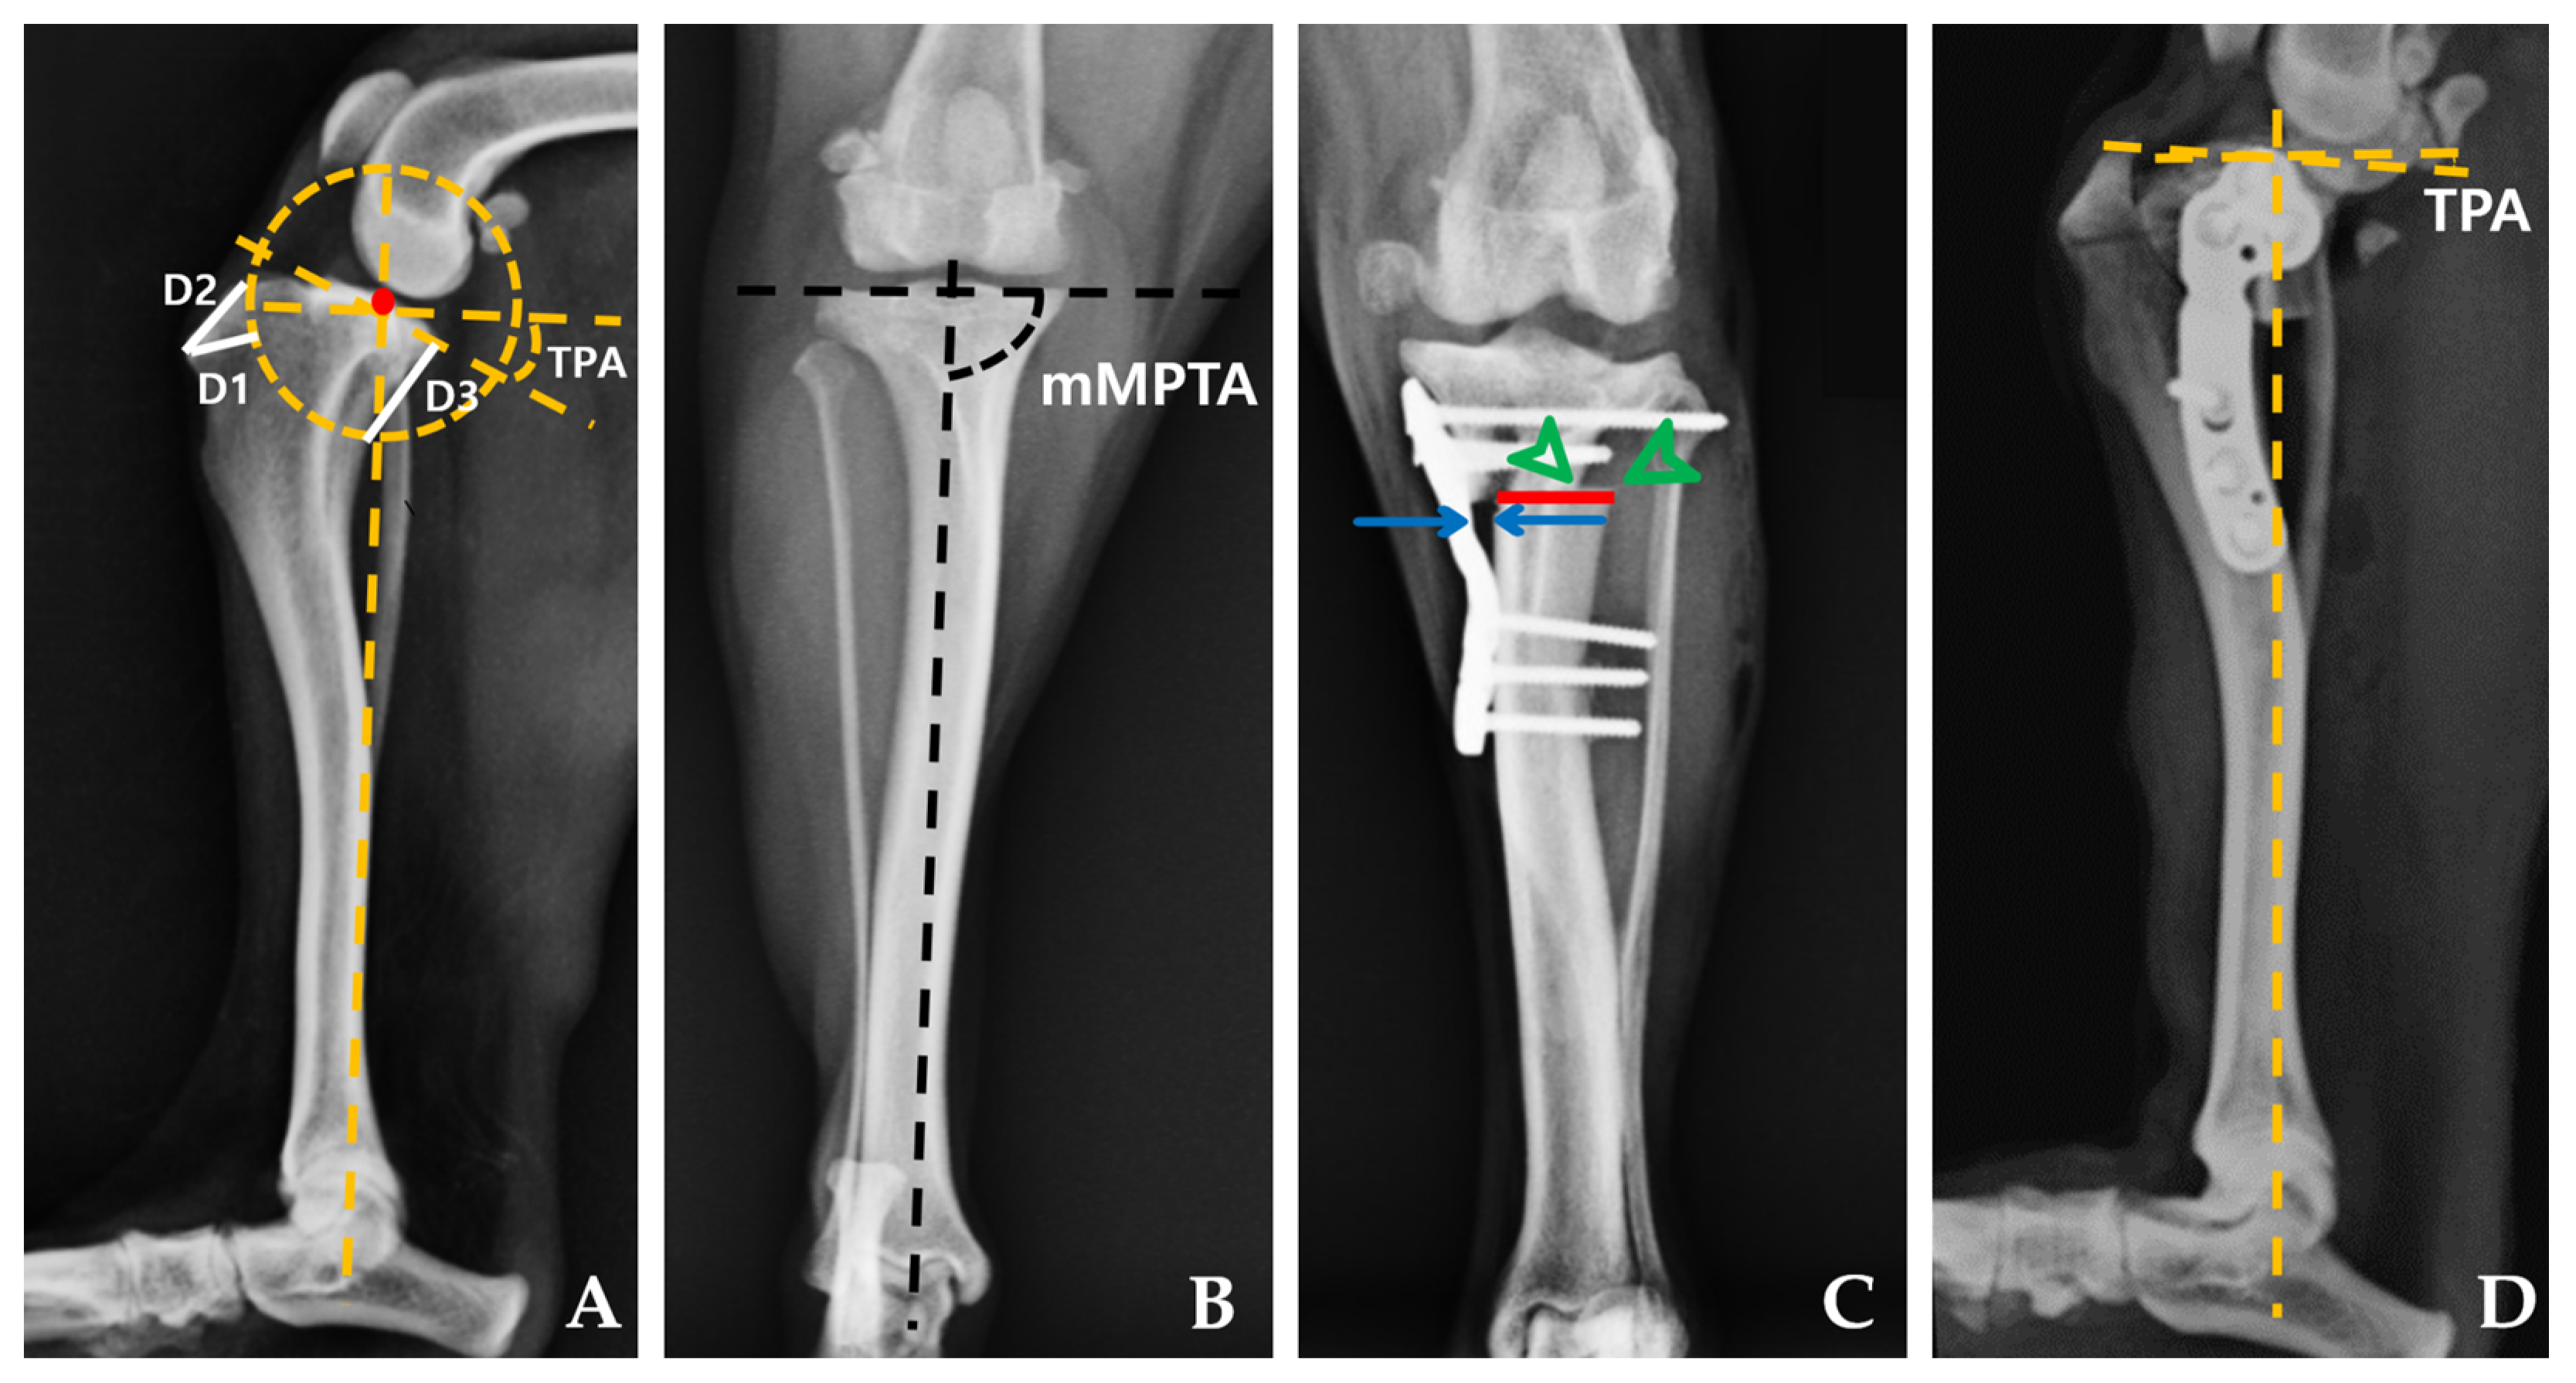

2.4.1. Radiographic Measurements